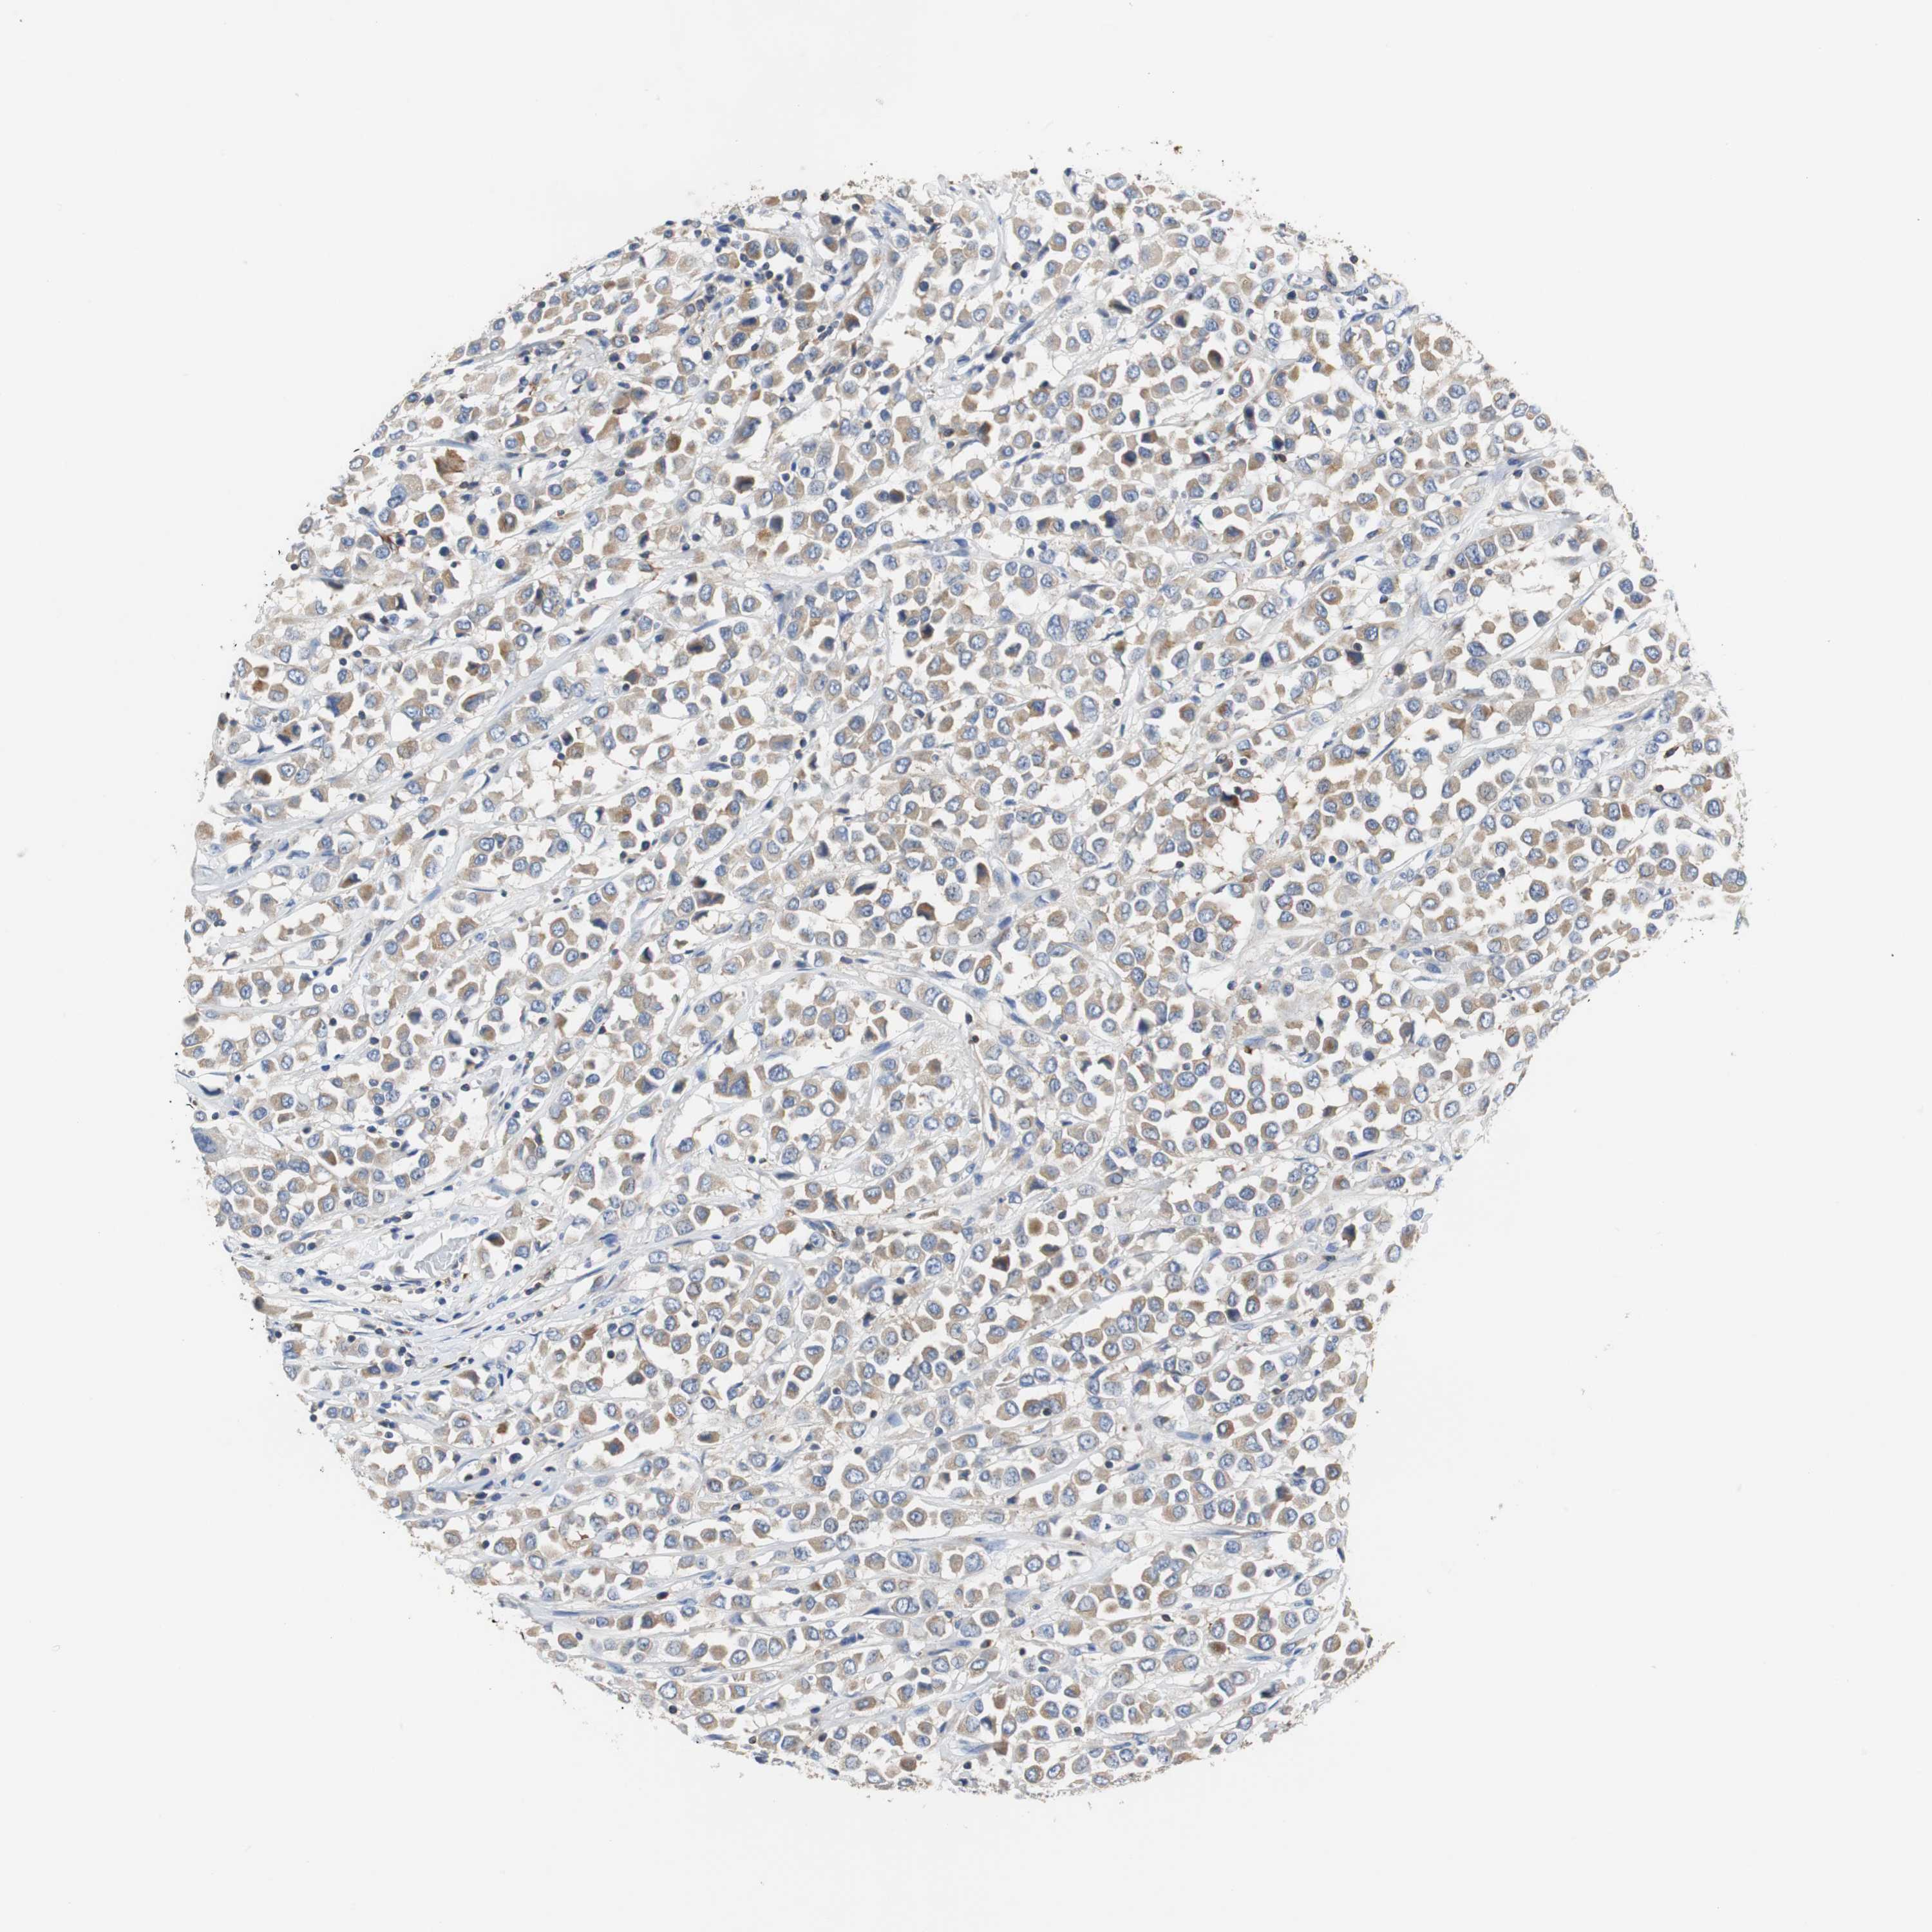

BRCA TCGA BRCA VALIDATION PROTEIN EXPRESSION